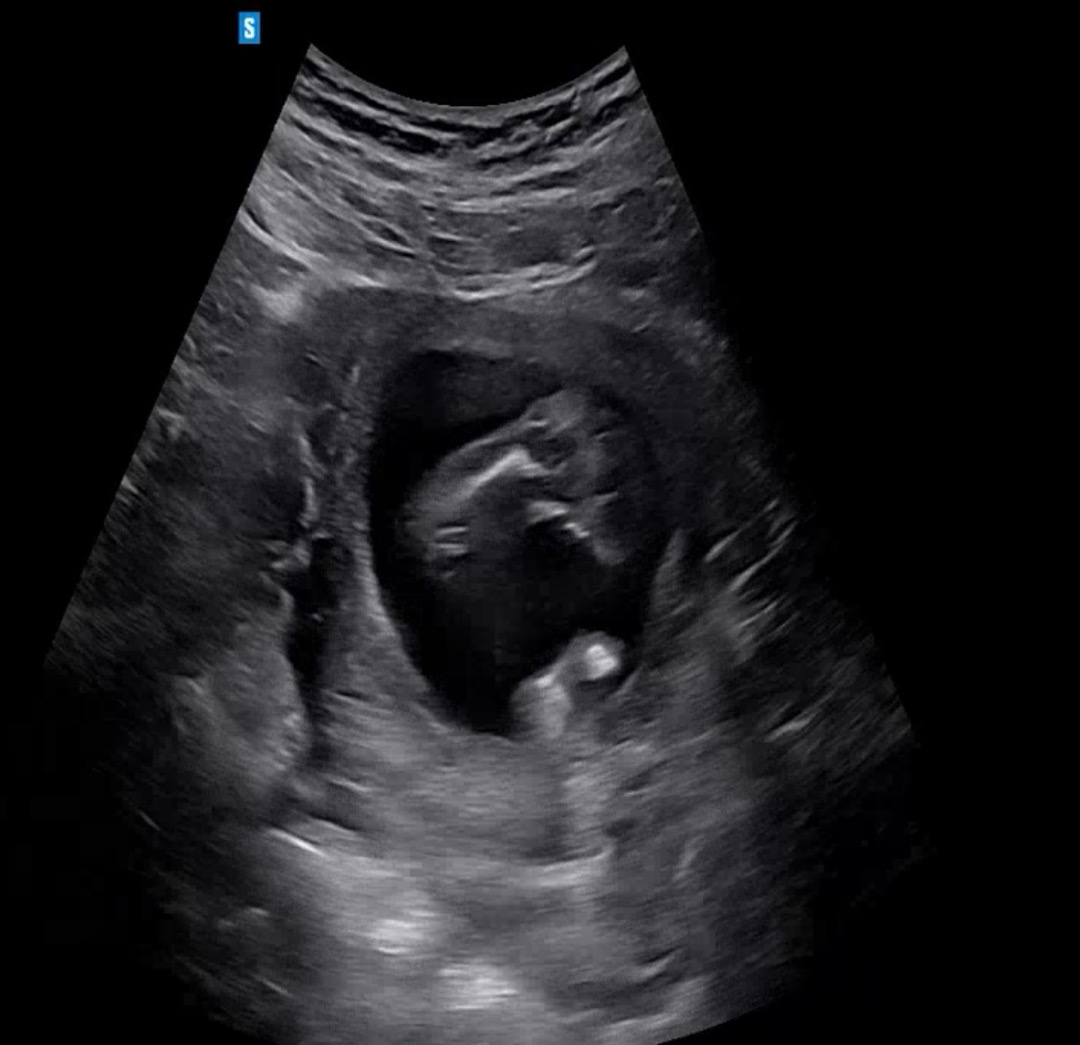

16주차에 초음파 보고 왔는데 여아일까요 남아일까요??? 다른분들은 선명하게 보이시던데 제 초음파는 좀 흐리게 보여서요 배동님들이 보시기에 어때 보이시나요 ㅜㅠ 너무 궁금해요